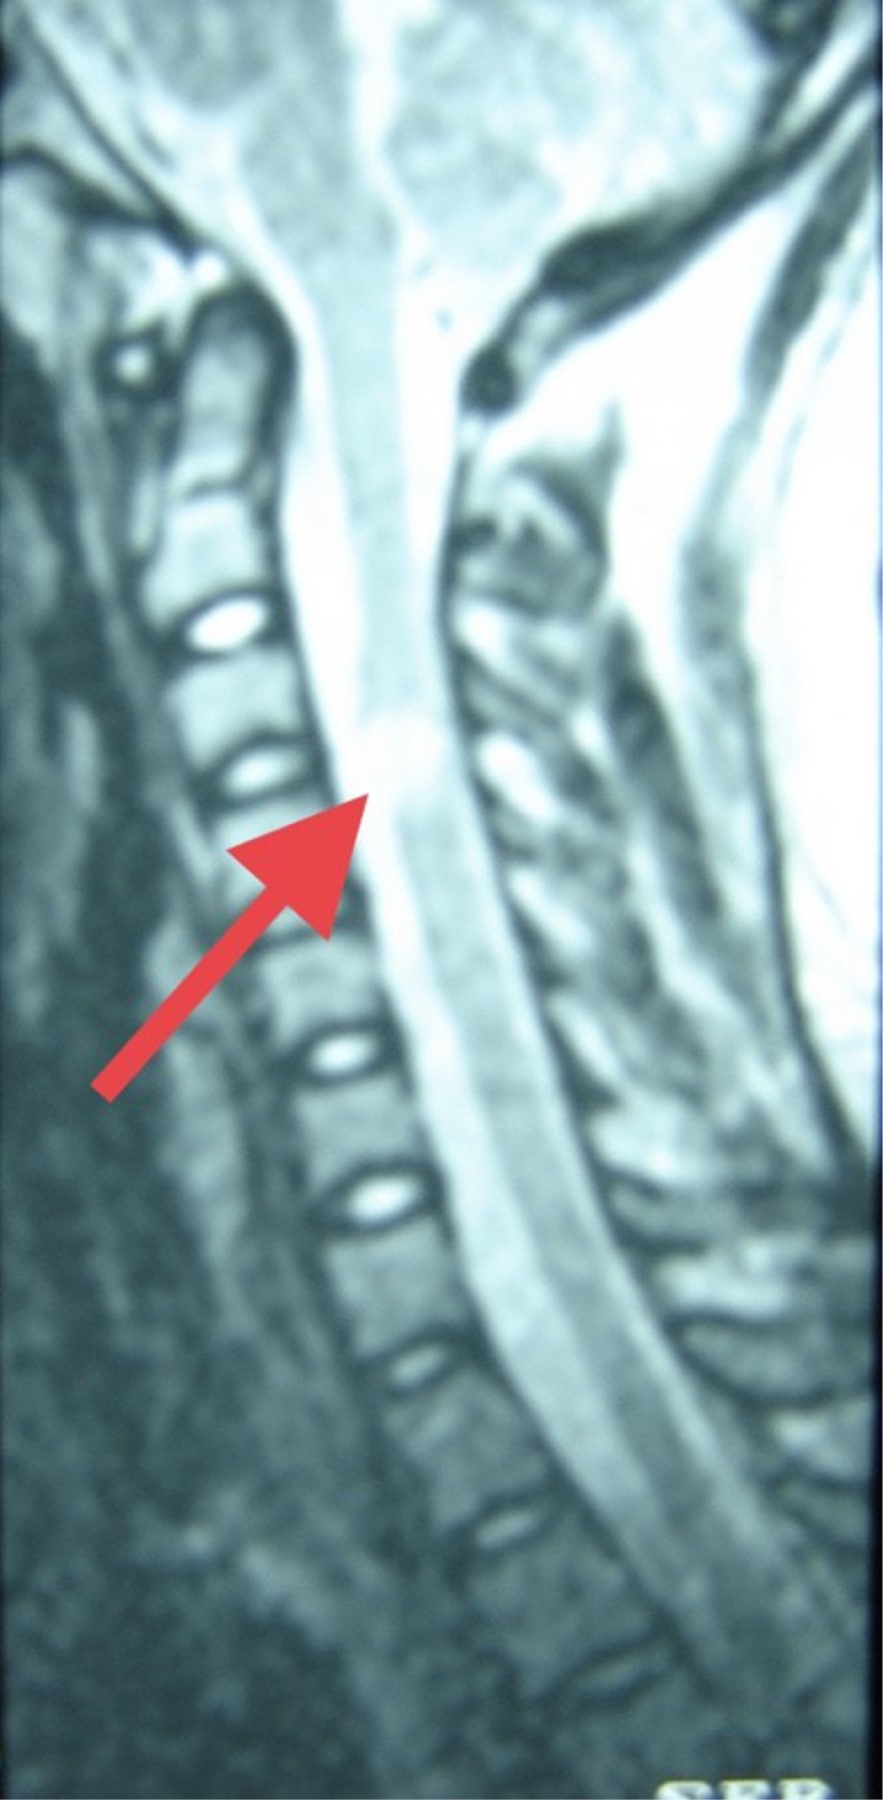

Objective: We describe two adolescent patients with multiple sclerosis, which is a demyelinating disease of the central nervous system. Presentation of the cases: The first case was a 14-year-old female patient with overweight; her condition was characterized by dizziness, headache, paresthesia in the lower limbs, diplopia and bradylalia. On physical examination, compatible data of cerebellar involvement were identified. A magnetic resonance imaging (MRI) of the skull showed areas of demyelination in the posterior fossa. Multiple sclerosis, the relapsing-remitting variety, is diagnosed. After the administration of steroids and beta interferon, there was improvement in symptoms. Second case: 13-year-old female, who presented fall from her own height, bladder incontinence, loss of strength in the left arm and leg. On physical examination, left hemiparesis was detected. MRI: demyelination data in lateral ventricle, cerebellum and spinal cord. The patient improved after starting steroids and interferon. Conclusions: The clinical presentation of multiple sclerosis in pediatric patients is a challenge, since it is a condition with unspecific manifestations. Establishing the diagnosis requires multiple studies. The earlier treatment is started, the more favorable the prognosis.

Figure 6